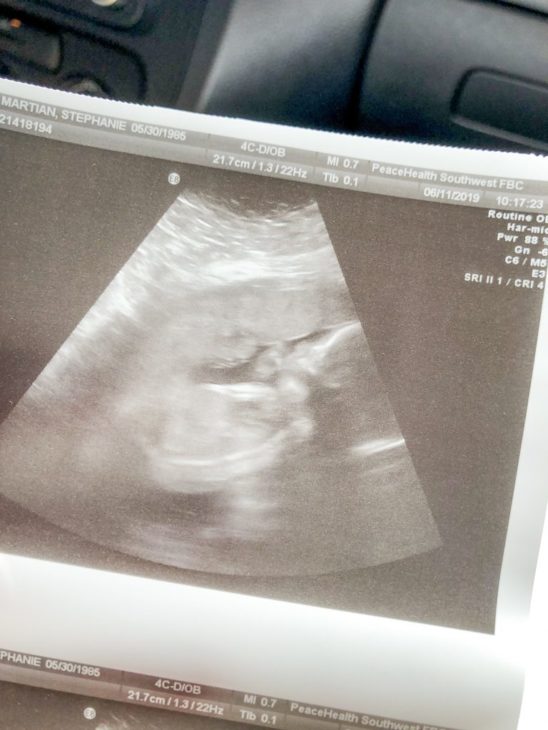

They performed an ultrasound in which they said she was overdramatic because of the way she kept turning her back whenever they tried to snap a picture of her face. That’s 100% me. We saw her practicing her breathing, which was my favorite part.

So yeah. Here’s a picture of our little overdramatic overachiever from that day: